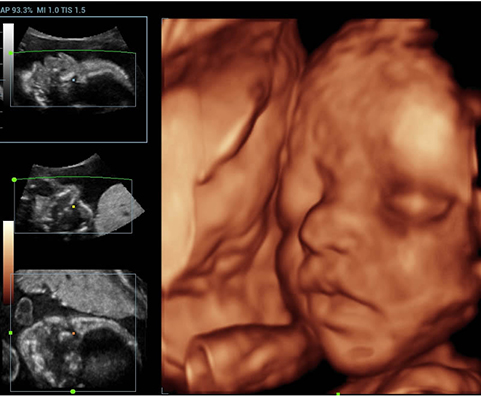

Sejak didirikan, Mindray terus mencari cara baru untuk meningkatkan keandalan diagnostik. Didukung Teknologi ZONE Sonography? terkini, platform ZST+ baru Resona 7 meningkatkan kualitas gambar ultrasound melalui pengambilan zona dan pemrosesan data saluran.

Selain kualitas gambar premium, Resona 7 juga meningkatkan kemampuan penelitian klinis dengan V Flow revolusioner untuk evaluasi hemodinamika vaskular, serta pengambilan penampang tercanggih dari rangkaian data 3D untuk diagnosis CNS pada janin. Kombinasi pengoperasian multisentuh berbasis gerakan yang paling intuitif dengan semua fitur klinis penting membuat Resona 7 menjadi gebrakan baru dalam inovasi ultrasound.